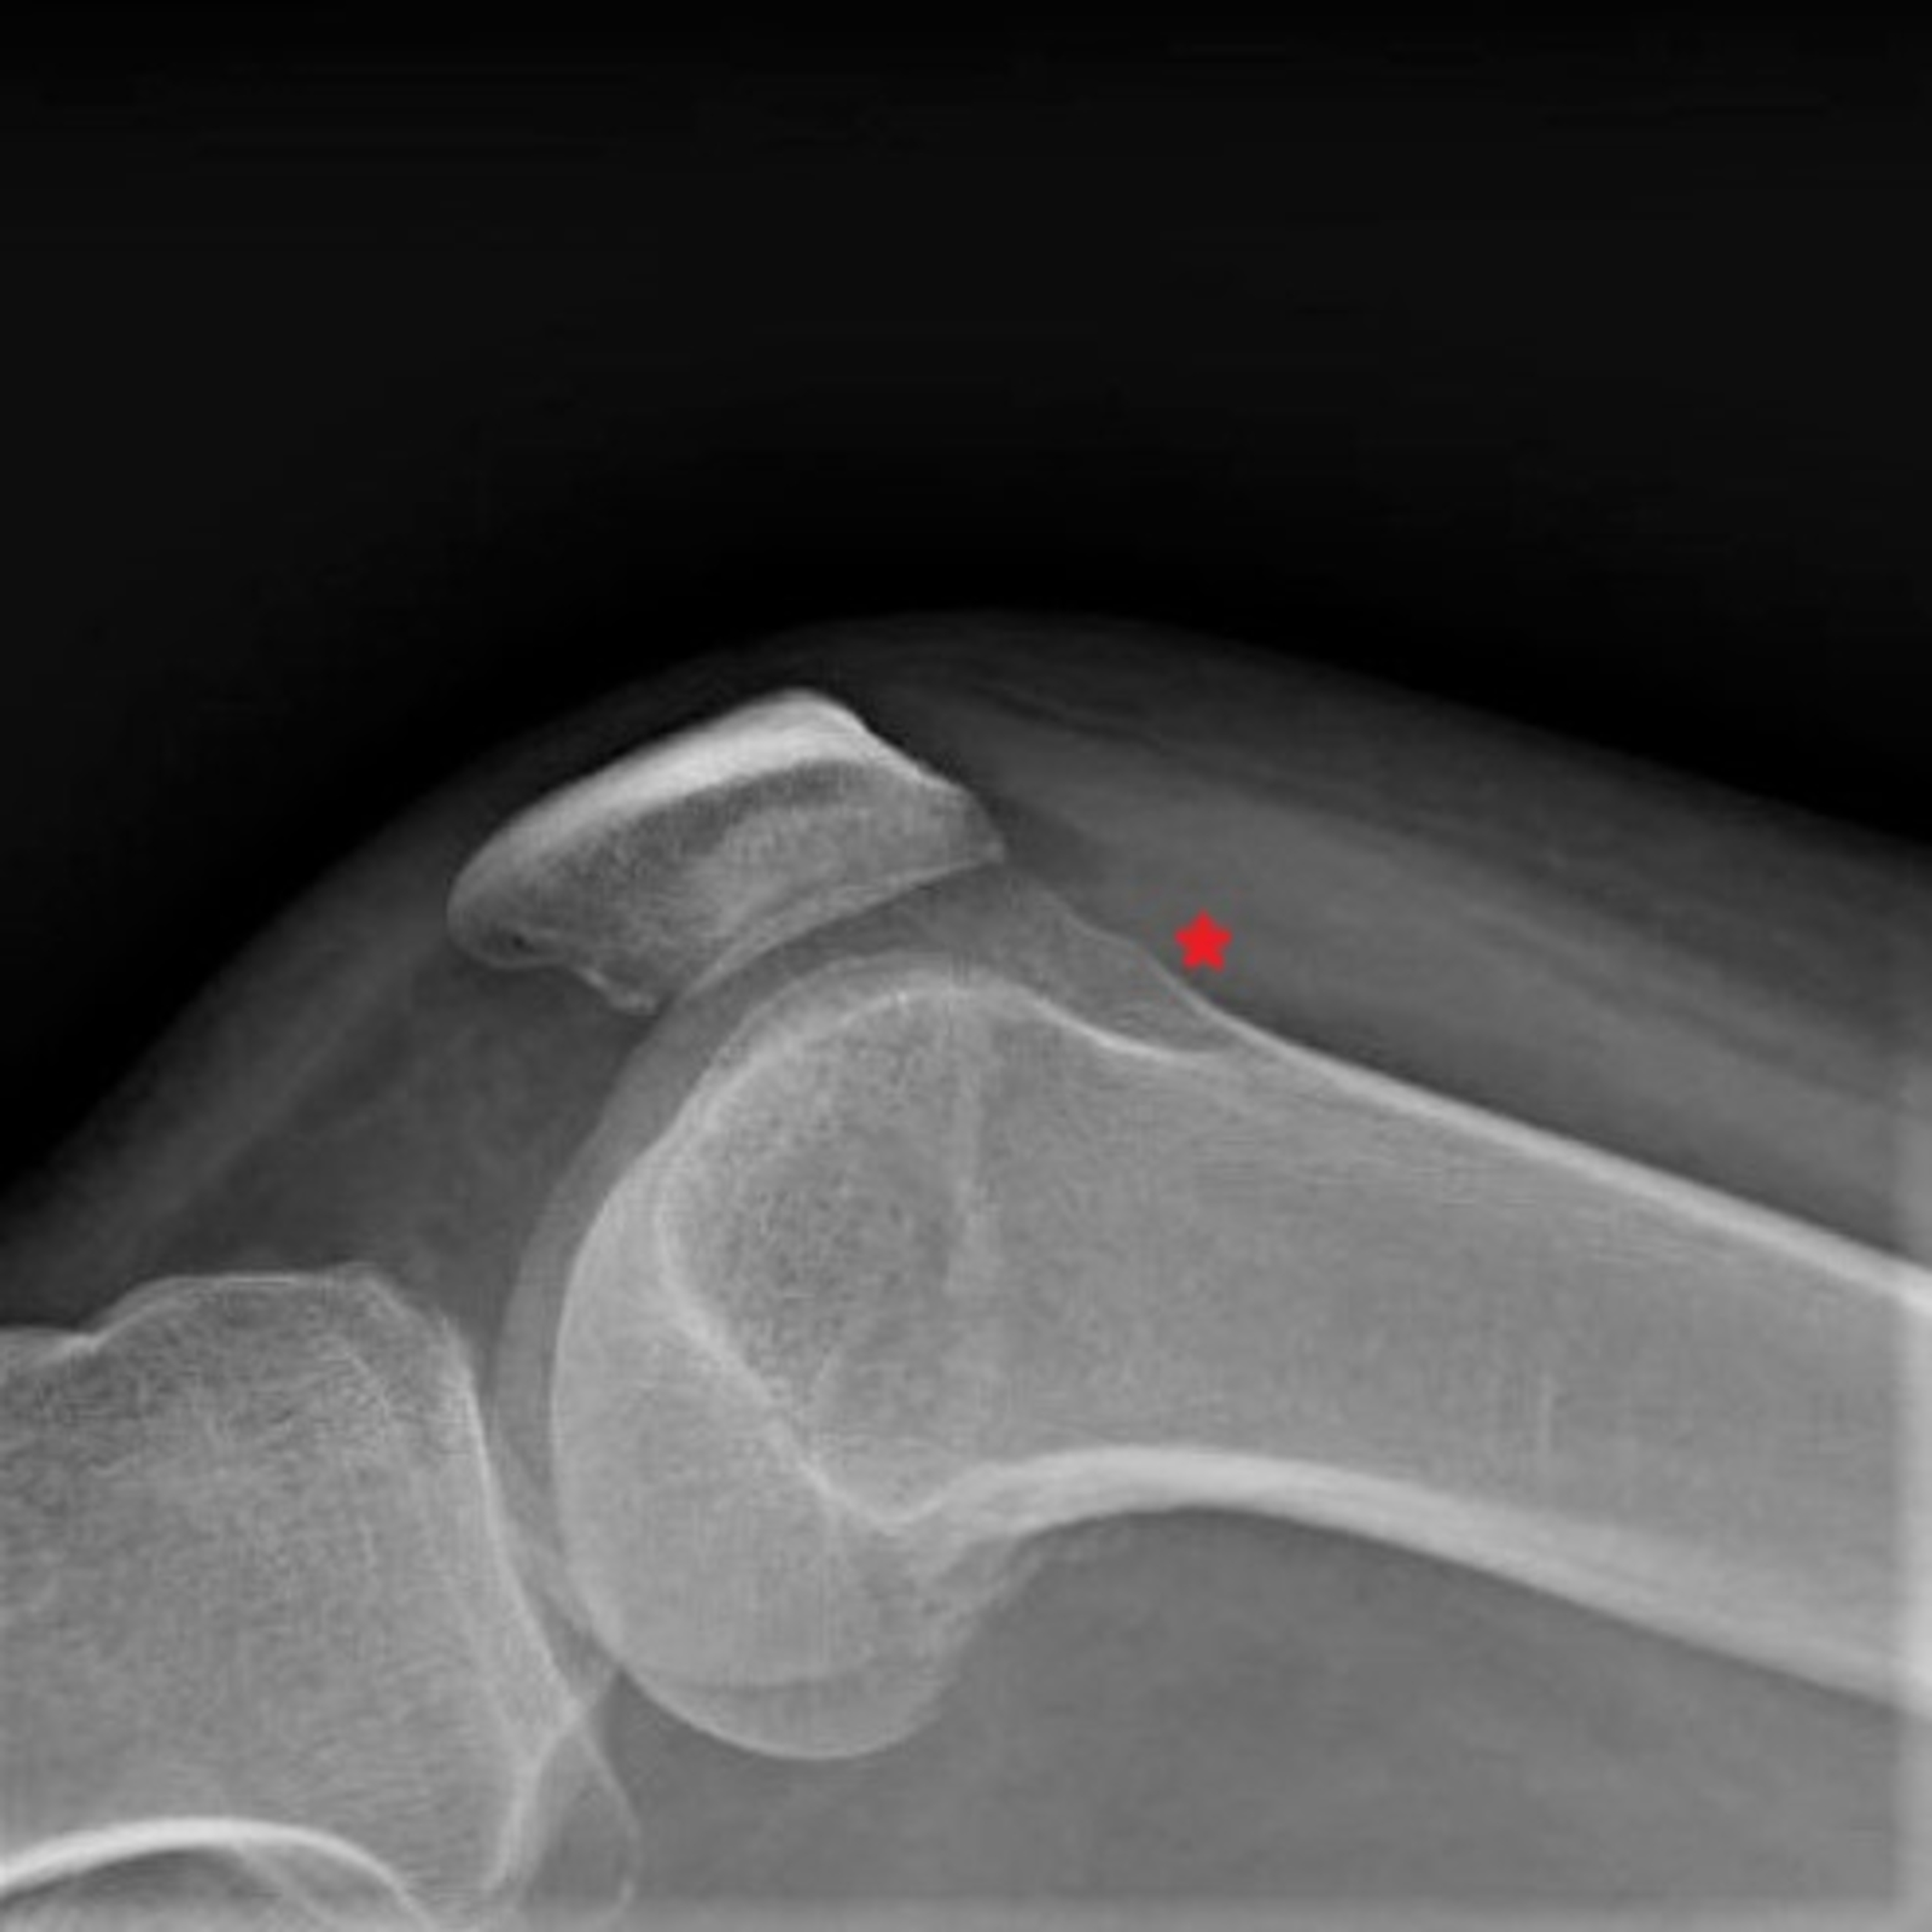

Atypical Salmonella Septic Arthritis of the Shoulder in a Yo Salmonella Arthritis Salmonella septic arthritis is a rare entity with cases mostly prevalent in patients with sickle cell disease, immunocompromised state,. Salmonella infection is a common bacterial disease that affects the intestinal tract and can cause diarrhea, fever and stomach cramps. Doing these things help you avoid the many foodborne bacteria that can cause reactive arthritis, including salmonella, shigella,. Some people may. Salmonella Arthritis.

From www.semanticscholar.org